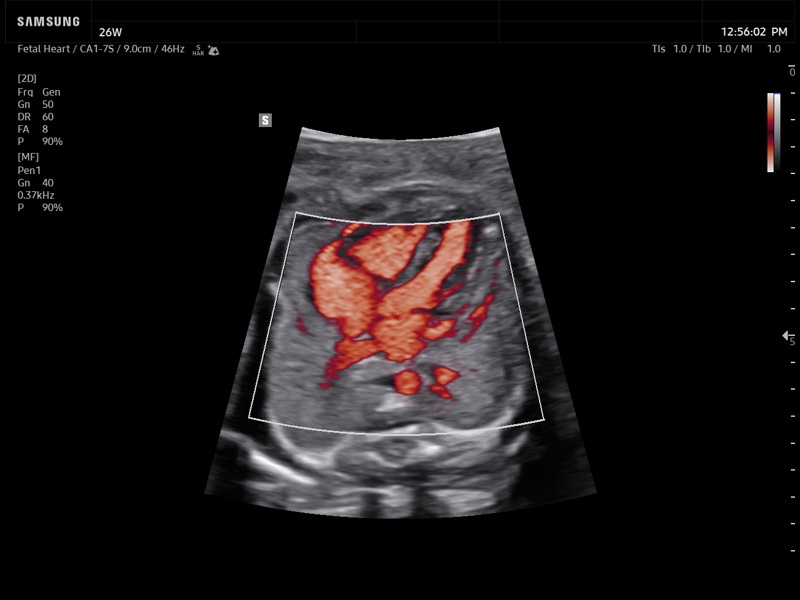

Fetal heart, MV-Flow™

Fetal heart, MV-Flow™ (echogramm №936)

[RU] Ultrasound image №936: Fetal heart in MV-Flow™ mode (microcirculation visualization). 26 week, convex probe 1-7 MHz.

Echogramm was received by ultrasound scanner Z20 (new model).